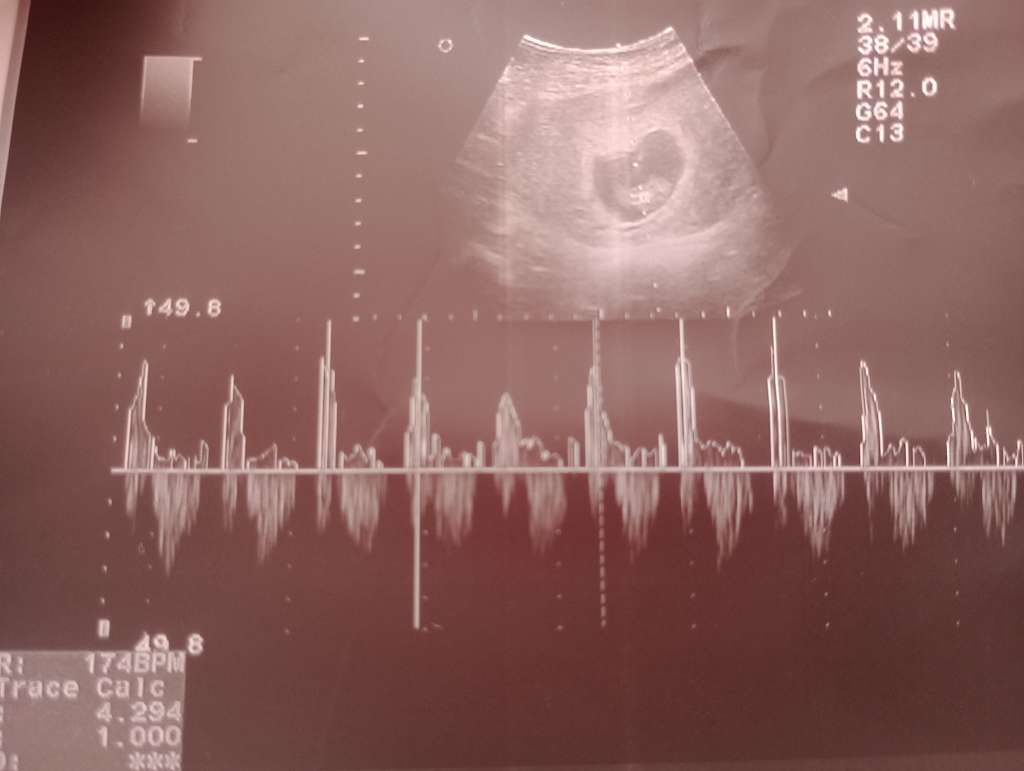

Z tymi cyklami u mnie to nie takie proste, bo u mnie każdy wyglądał innaczej. Na pierwszej wizycie lekarz powiedział mi, ze to około 4 tydzień, napewno nie około 6 jakby wychodziło z OM. I wg tego wydedukowalam sobie kiedy mniejwiecej doszło do tego zbliżenia i ta date wzielam jako punkt wyjścia i wg tego wyliczyalam sobie tydzień ciąży

Trochę to skomplikowane, ale dziś się okaże tak naprawde, bo lekarz powiedział ze na początku ciąży po wymiarach itd może określić łatwo co do dnia. Gorzej jak kobieta np w połowie ciąży nagle zorientuje się, ze chyba jest w ciąży i przyjdzie w dwudziestym którymś tygodniu

To wtedy już nie ma takiej możliwości.